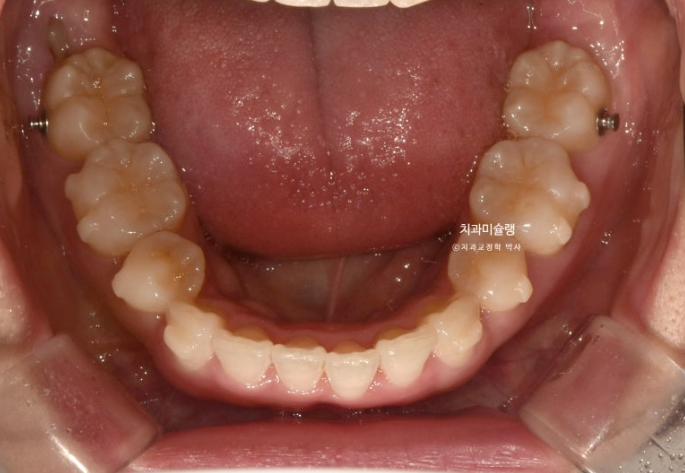

약 한달간의 추가장치 제작기간을 기다려 24년 6월부터 10월까지 23개 추가장치를 모두 낀 후 모습입니다.

24.10

추가장치 치료기간 동안 환자분은 예전처럼 열심히 끼지는 못했고 고무줄도 하루종일 껴주기를 당부드렸지만 개인사정으로 인해 잘때만 착용했습니다.

그래서 6개월이나 추가장치를 꼈지만 과개교합이 그대로 남아있고

발치공간이 놀랍도록 그대로 남아있는 모습입니다.